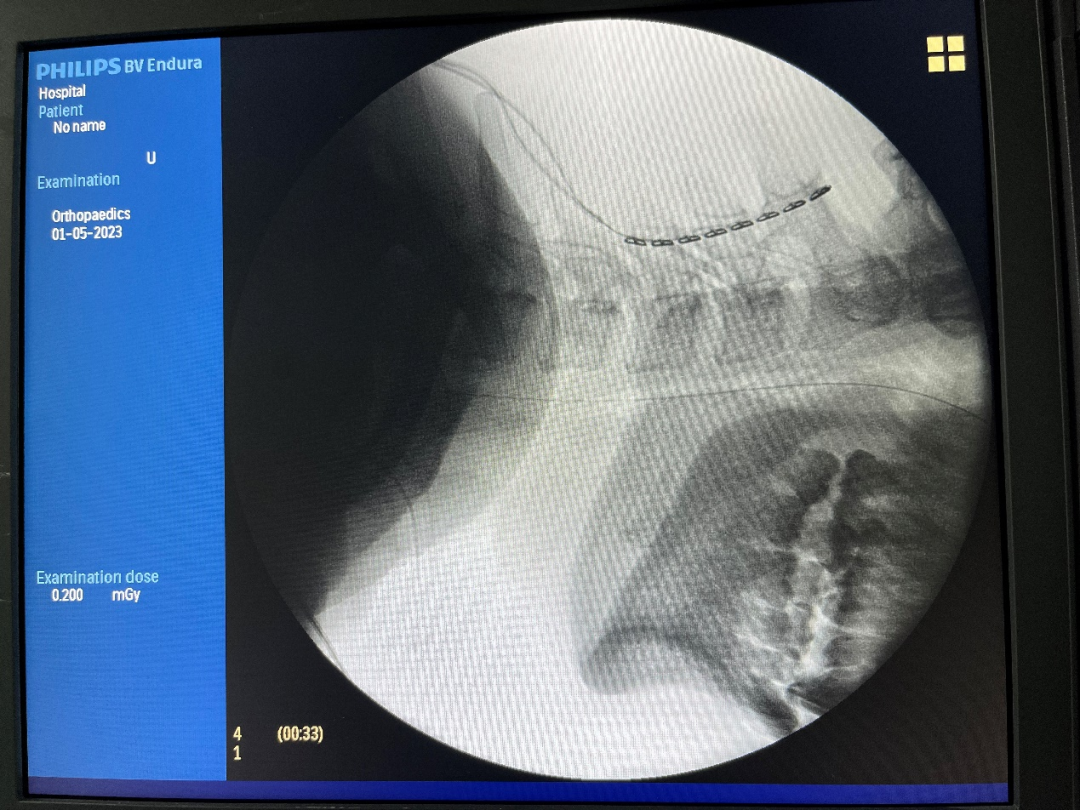

术中显示电极位置放置良好